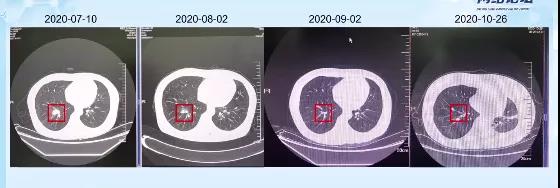

2020-08-02患者因需进行第二次化疗住院,检查发现患者各项肿瘤指标明显下降,肺部肿瘤组织明显缩小,体格检查较之前也有明显好转,疗效评估部分缓解(PR)。

2020-09-02患者因需进行第三次化疗住院。患者乏力症状虽然比治疗前好转,但是较第二次住院时并没有改善,同时头晕症状依旧明显。不过患者的神经系统还是有改善的,肿瘤相关指标也持续降低,胸部CT提示患者肿瘤组织进一步缩小,疗效评估PR。

2020-10-26因患者需进行第四次化疗再次住院,患者头晕、乏力症状仍时有发生,但是各项体格检查以及神经状态还算正常。肿瘤指标稳定,胸部CT显示病灶依旧缩小,疗效评估PR。

2020-10-28开始第四周期治疗。患者由于反复头晕,不能排除免疫性脑炎,故此次未行免疫治疗,停用度伐利尤单抗,改用依托泊苷0.1mg d1-d3 + 顺铂40mg d1-d2。